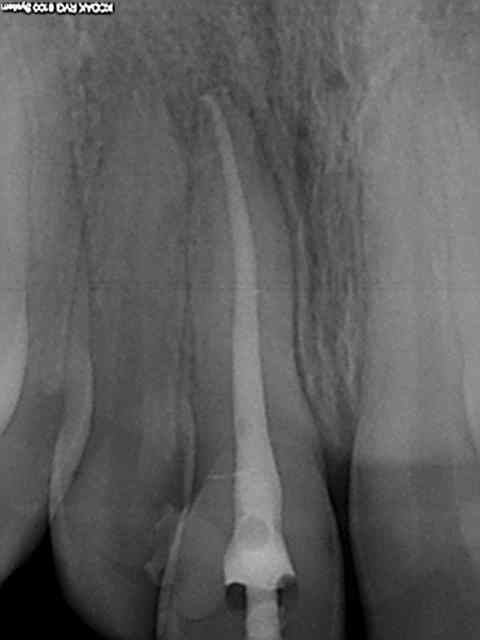

Radio initiale, cone en place , cone scellé, radio du bouchon apical réalisé au système b, puis radio finale après thermo-condensation. C'est obligatoire avec la nouvelle CCAM. Fini de jouer au dentiste le 1er juin.)))))))

Elles sont dans le désordre , remets les en ordre ( ca fait partie d'un qcm de formation continue) vu que le niveau de la formation initiale semble resté bloqué dans les années 80.